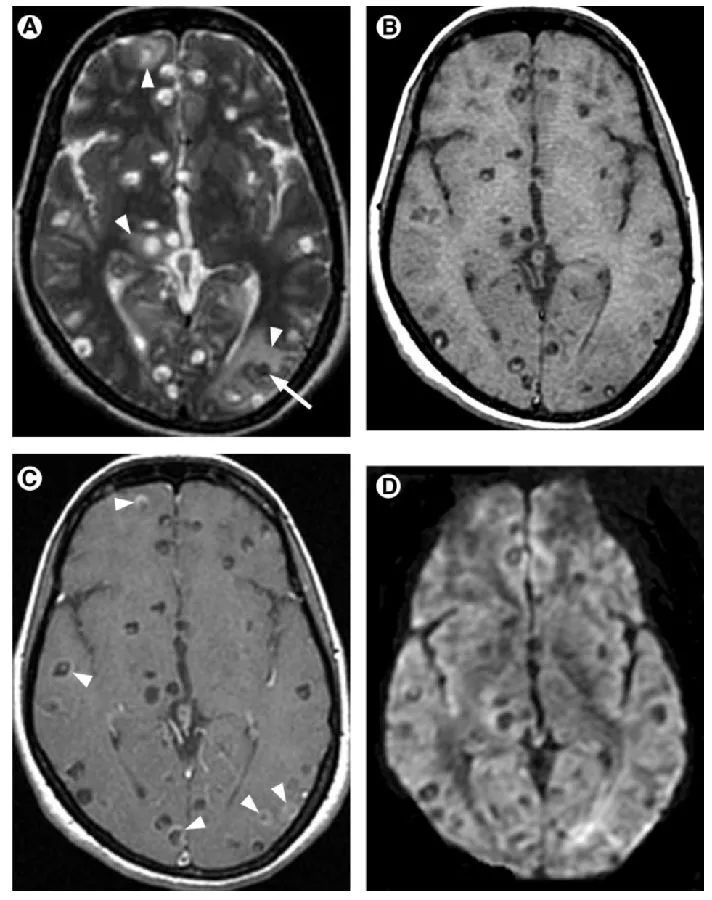

大脑里面「凹造型」:常见神经系统寄生虫感染影像表现

脑寄生虫病的影像诊断辅导二(20201126)